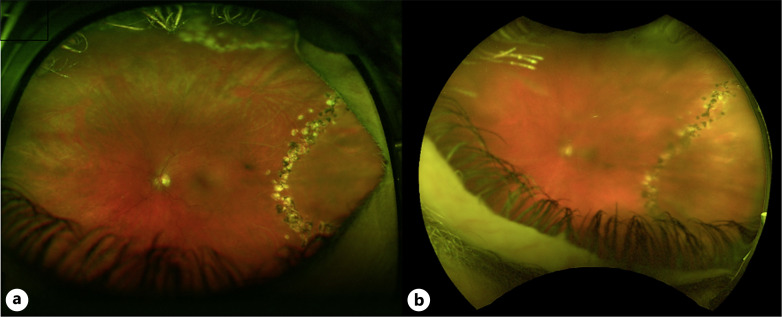

Introduction: Demarcation laser photocoagulation (DLP) is an infrequently utilized modality for limited retinal detachments. The current study, a retrospective consecutive case series, reviewed anatomic and visual outcomes in these patients at a single academic center.

Case presentations: A search of the electronic medical record identified 10 eyes of 10 patients. Five of the 10 patients were asymptomatic at the time of initial treatment. Five patients had symptoms corresponding to retinal detachment. The asymptomatic patients remained stable without progression at the last follow-up (range 1-8 years). In 2 of 5 symptomatic patients, the retinal detachment progressed through the laser demarcation and, subsequently, underwent vitreoretinal surgery. At the last follow-up, the retina was attached in all five symptomatic patients.

Conclusion: In this small series of patients undergoing DLP, the retina remained stable in asymptomatic patients but the retinal detachment progressed through the laser demarcation in the majority of symptomatic patients.